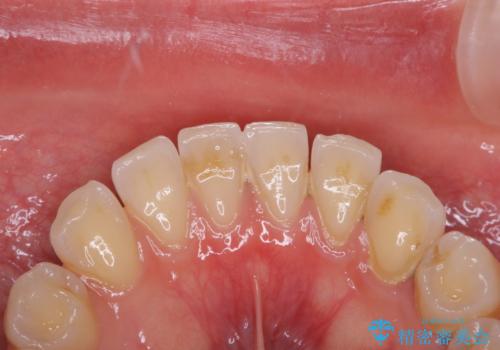

プラーク(細菌の塊)や歯石がたまると歯の表面はザラつきいてきます。そのザラつきは歯周病や虫歯菌の棲家となります。そのまま放置すると、歯肉が腫れてきたり、歯肉から出血したり、口臭が強くでたりします。とくに歯肉の境目は、歯磨きで汚れを除去することが難しく、プラーク(細菌の塊)や歯石が溜まりやすい場所です。

歯並が、がたついている場合はなおさら汚れが溜まりやすいです。矯正治療前や矯正中、定期的にPMTCをすることで、矯正治療中の歯肉トラブルを防ぐことにつながります。